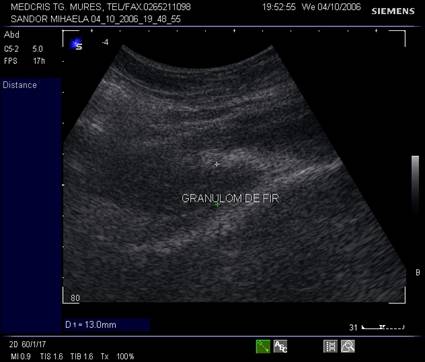

Fig. nr.355. La ecografia peretelui abdominal, o formatiune inomogena , prost delimitata in zona fasciei - un granulom de fir dupa o interventie chirurgicala